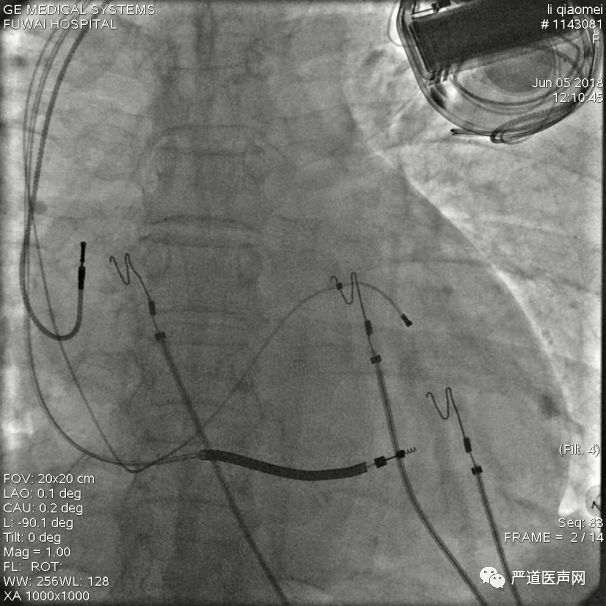

最终影像

AP

LAO

RAO